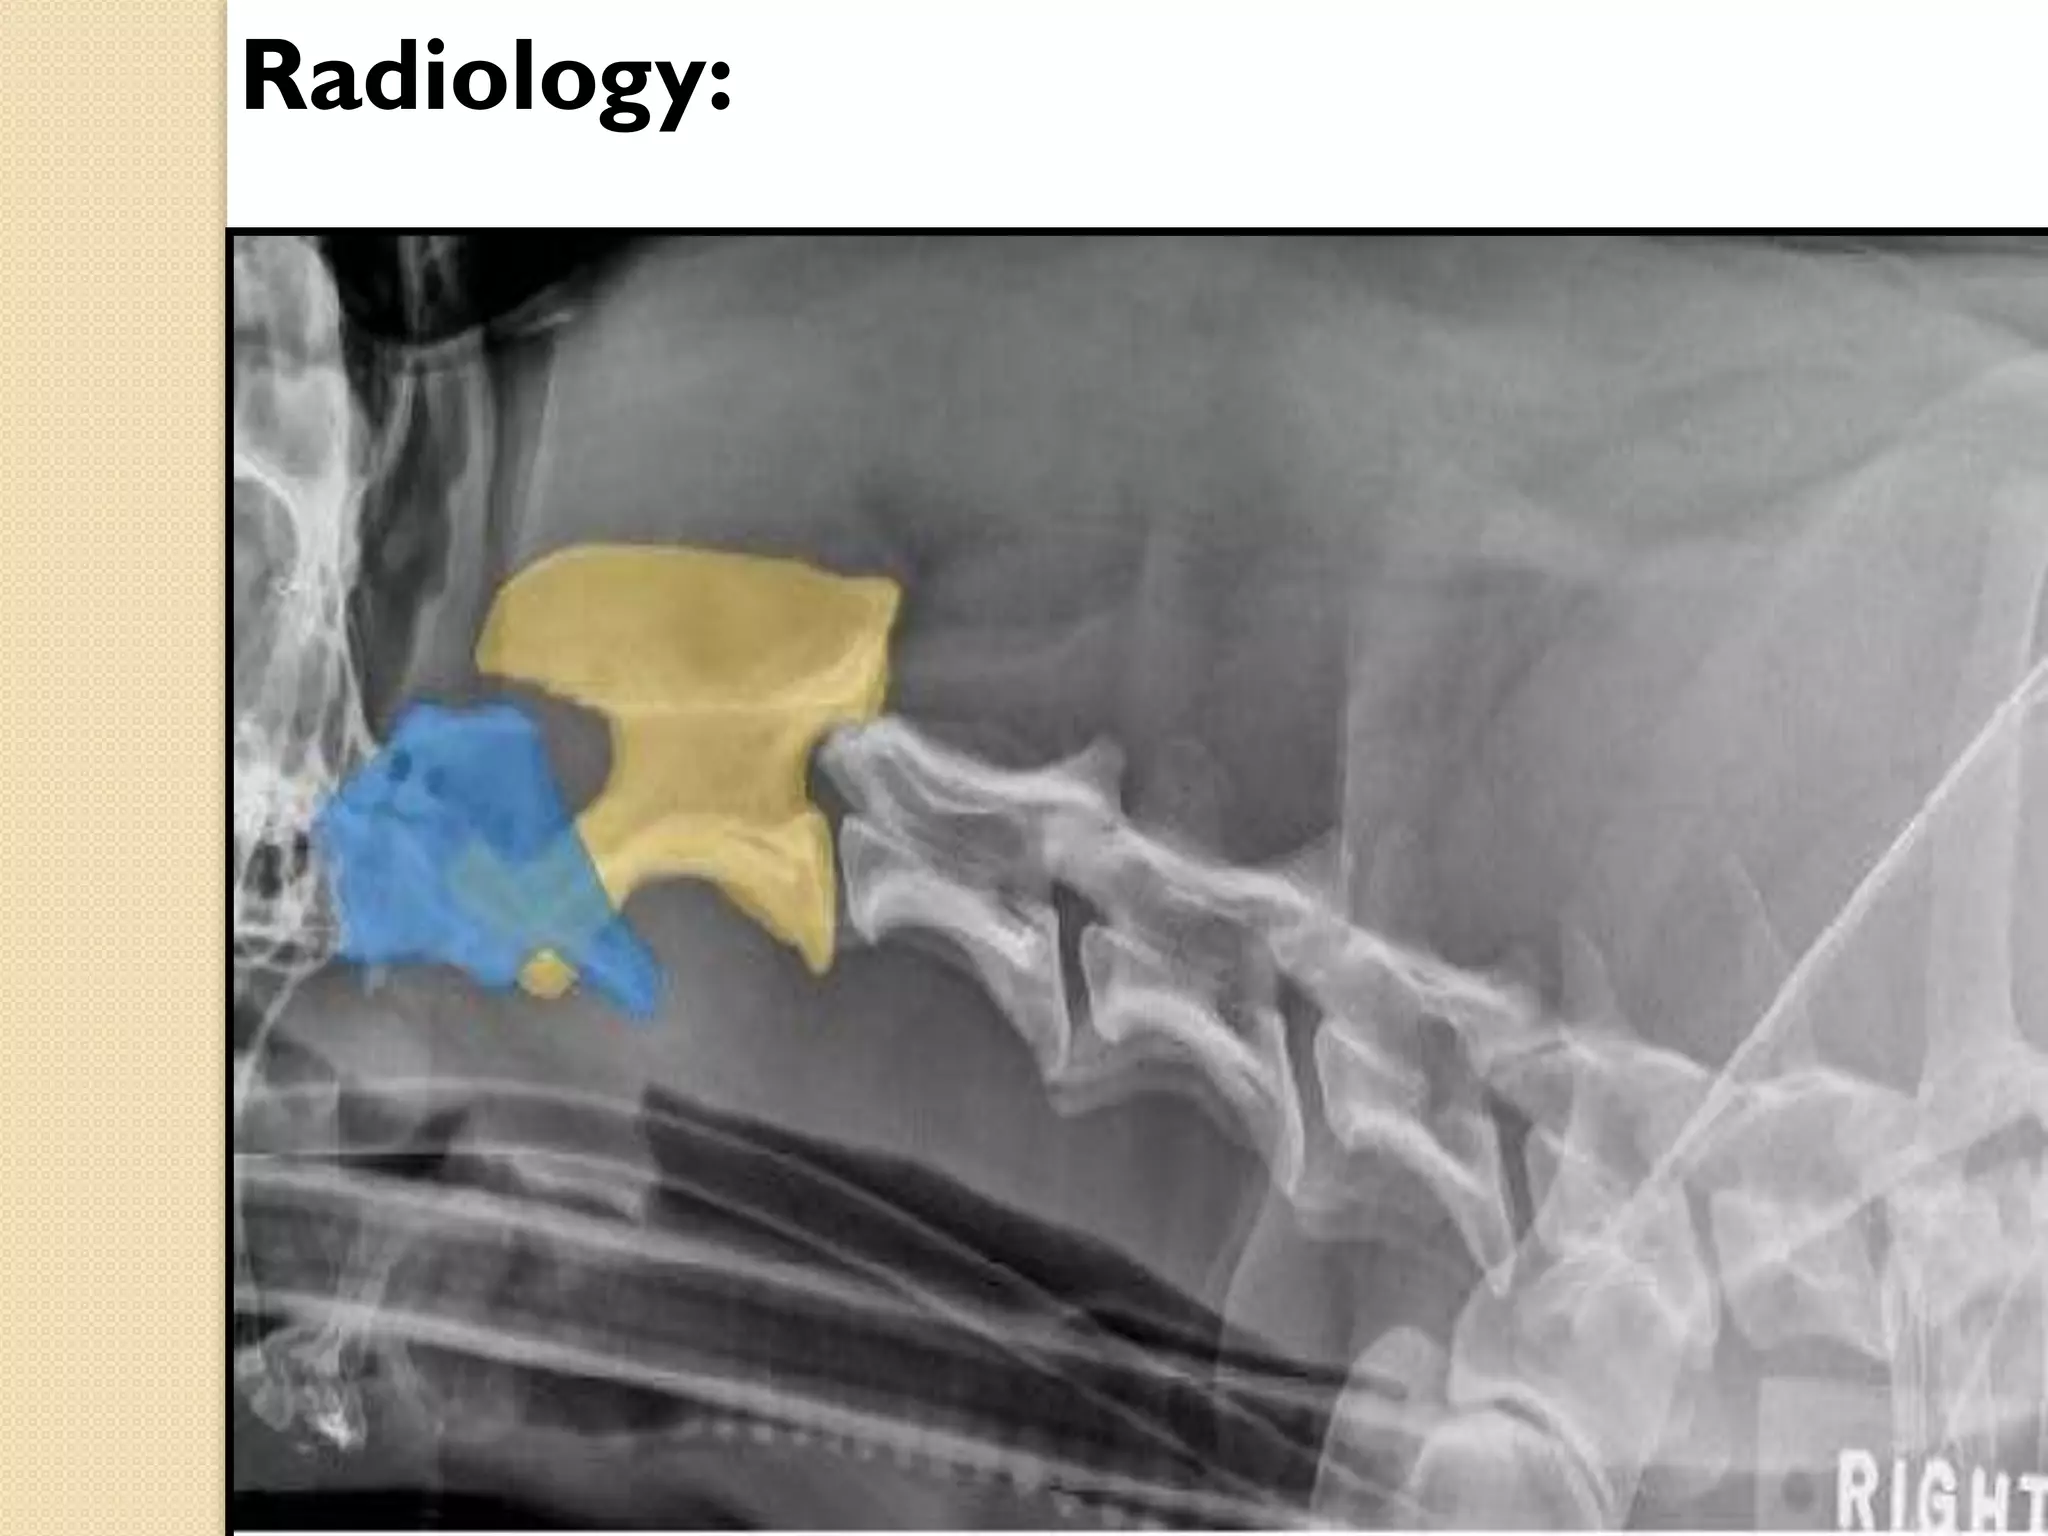

Atlas

Axis

Radiology:

Thoracic vertebrae: